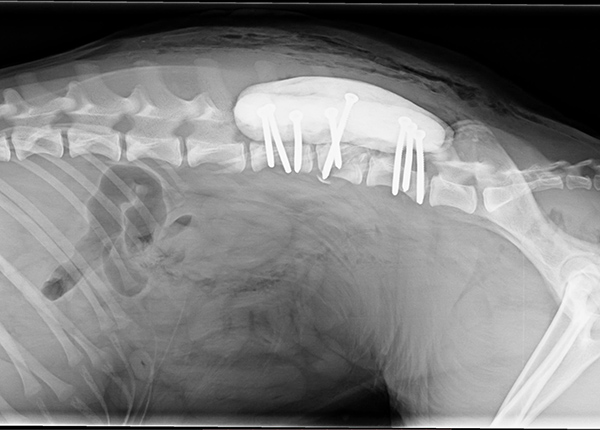

- ošetření zlomenin

- vnitřní osteosyntézou